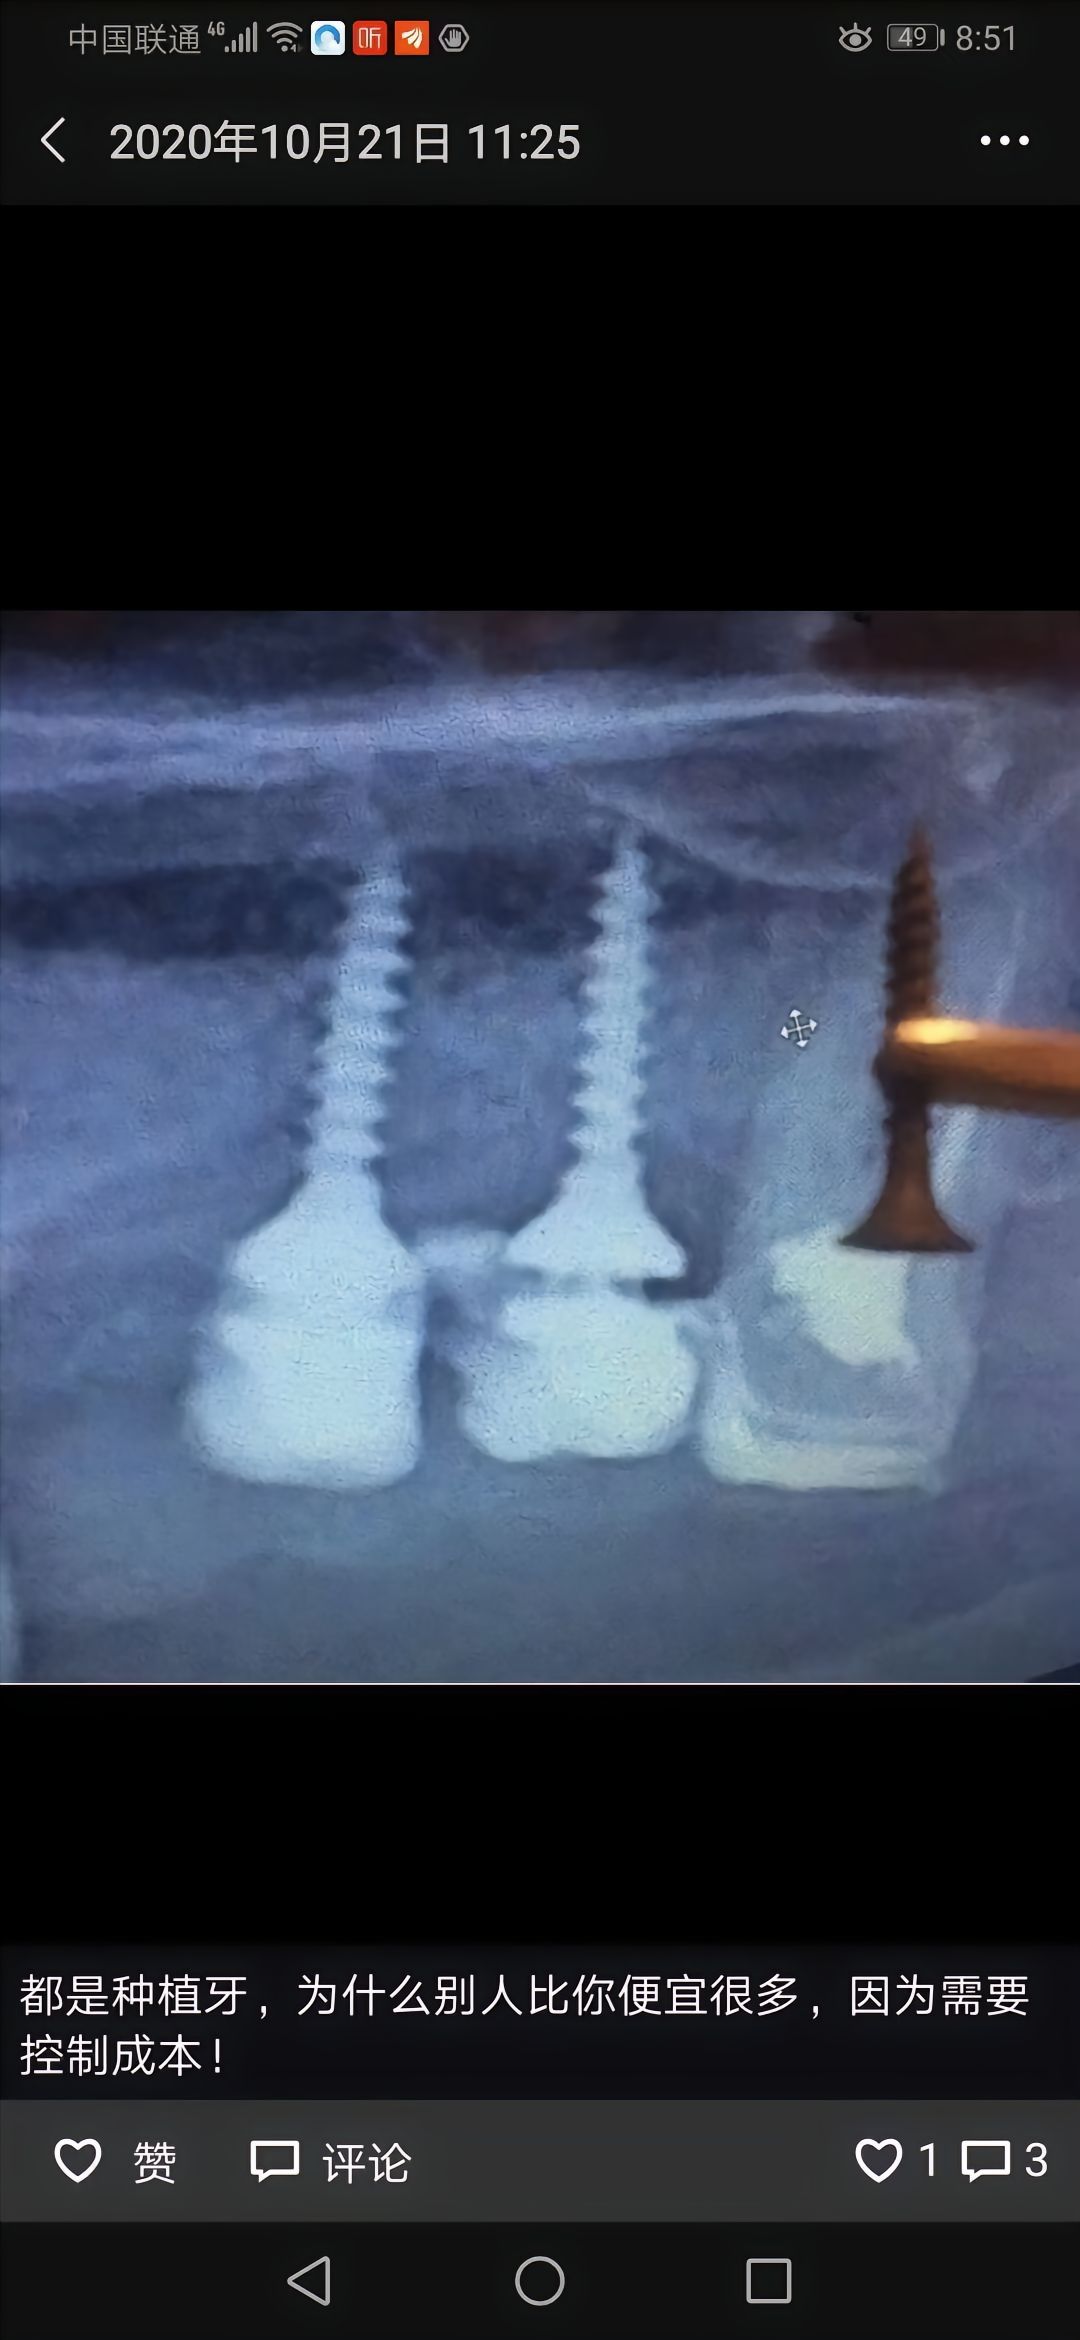

什么奇葩都有

不知道说什么了。